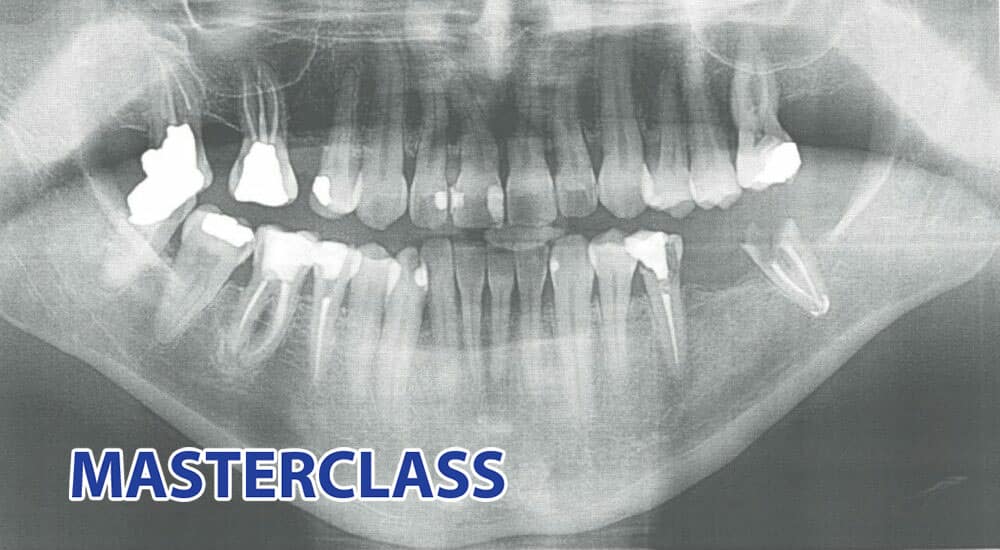

Endodontie : comment traiter les canaux courbes ou calcifiés ?

Les canaux courbes et/ou calcifiés sont toujours un challenge. Chaque chirurgien-dentiste, de l’omnipraticien débutant à l’endodontiste confirmé, rencontrera les mêmes difficultés. Les instruments utilisés ici sont d’ailleurs tous en vente libre. Pour résumer, il n’y a pas de recette secrète, ni de formule magique, seulement des protocoles déjà anciens mais toujours utiles....